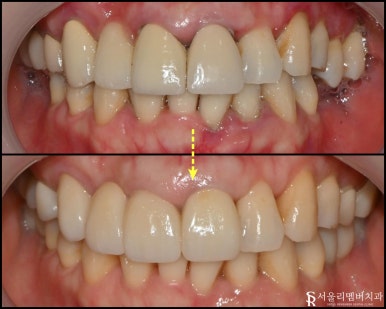

최종 보철

낙성대 치과 에 자체기공실에서

더 정확하고 고품질의 크라운을 제작해 드리는데요.

전후로 한번 보실까요?

이렇게 규칙이 잡혀있는 구강을 볼 수 있습니다.

마지막으로 전체적인 체크를 다시 해주고

접착 후 진료 마무리했습니다.

어금니가 없던 환자는 밥 먹는 게

이렇게 편한지 몰랐다면서 찾아오셨는데요.

실제로 환자분 살이 오르셨답니다 :)